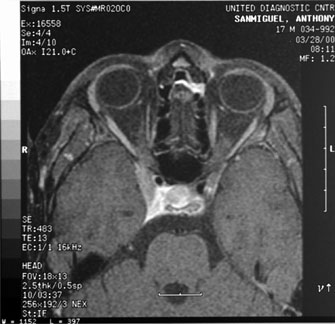

Anterior visual pathway gliomas account for the majority of intrinsic optic nerve tumors in childhood (Figs. 11, 12). Although they are true neoplasms, malignant features are extraordinarily rare in the pediatric population (see Chapter 5). Dutton58 provided a thorough review of this subject. When the glioma is initially confined to the optic nerve alone, the mortality rate is 5%. However, when the hypothalamus is involved, survival is less than 50% in some series. With a typically indolent course, these tumors generally can be managed conservatively, especially when confined to the optic nerve. Hoffman et al59 reviewed 62 cases of optic pathway/hypothalamic gliomas over a 14-year period, with 48 of these exhibiting relative stability with only visual defects: six patients had significant neurologic abnormalities, and eight died. Gayre et al60 reported a series of 42 patients with optic gliomas seen over 28 years at a single institution. Two-thirds were female, and slightly over half had neurofibromatosis type I (NF-1). Presenting signs and chiasmal involvement were similar in both NF (+) and NF (–) groups, the latter usually occurring within the first year after diagnosis. Regardless of treatment, the eye with better vision tended to remain stable over the long-term (and vision in the poorer eye often declined). Spontaneous regression of optic gliomas with visual improvement also has been reported.61,62

Fig. 11. Magnetic resonance imaging scans of optic gliomata. A. Marked enlargement of optic chiasm on coronal image. B. T1-weighted, gadolinium-enhanced image showing enlargement and marked enhancement of the right optic nerve and chiasm.